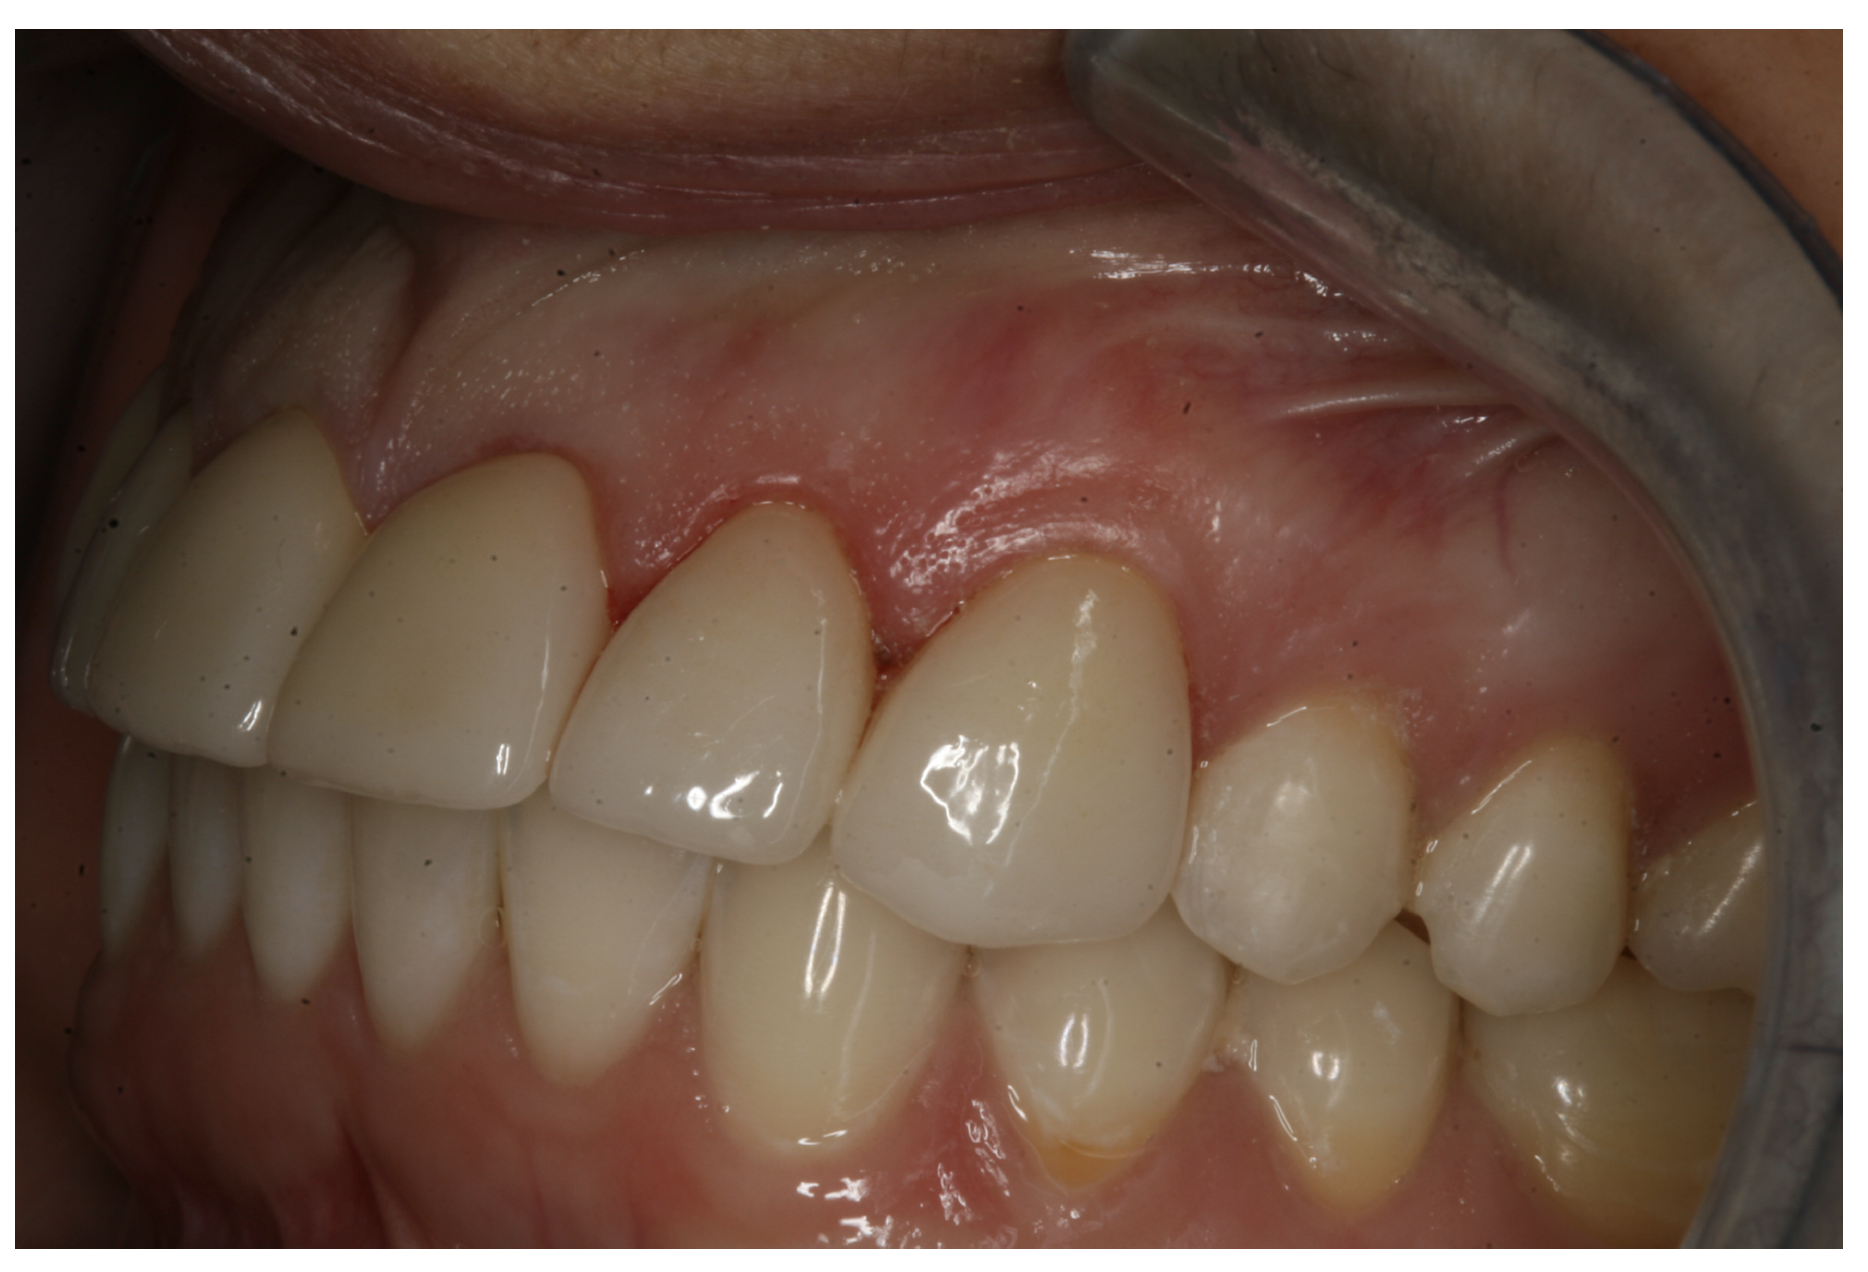

In another case, the patient presented with very thick, bulky, over-contoured veneers done on teeth Nos. 7 through 10 when she was a teenager. There also was some recession and staining at the margins (Figure 12). The clinician decided to restore teeth Nos. 6 through 11. A preparation design was required with provisionals removed. As tooth structure could not be regrown, the practitioner made the best of the situation. There was good gum health, which is important for isolation and marginal seal. The clinician cemented with a universal, doing six units at one time. Minimal cleanup was required. At a 1-month follow-up visit, although tissue still was settling in, the contours were natural. After a year (Figure 13), the gum filled in nicely and was in excellent health, and there was good color stability and seamless marginal integrity.